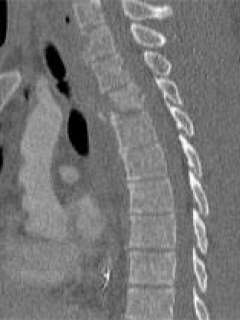

Jim is a motorcycle deputy in the Los Angles County Sheriff Department stationed in Malibu. While on patrol, he was struck by an automobile driven by a robbery suspect who was fleeing the scene of a crime. He was brought into the Ronald Reagan UCLA Medical Center Emergency Room with numerous severe injuries. He was immediately taken to the operating room by the general surgery service for treatment of a life threatening liver laceration. On examination he was noted to be unable to move his left leg, and had severe weakness of the right leg. CT and MRI scans disclosed that he had a serious spinal injury. He suffered a T5-6 fracture (mid-back) (Fig. 1), and a C6 fracture (neck). There was significant pressure on his spinal cord, and his spine was mechanically unstable. Without surgery, he virtually had no chance of regaining functional use of his legs, and the instability of his spine precluded him from sitting up.